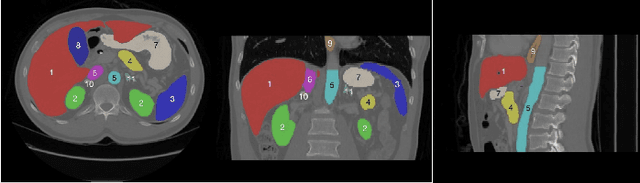

Abstract:The task of labeling multiple organs for segmentation is a complex and time-consuming process, resulting in a scarcity of comprehensively labeled multi-organ datasets while the emergence of numerous partially labeled datasets. Current methods are inadequate in effectively utilizing the supervised information available from these datasets, thereby impeding the progress in improving the segmentation accuracy. This paper proposes a two-stage multi-organ segmentation method based on mutual learning, aiming to improve multi-organ segmentation performance by complementing information among partially labeled datasets. In the first stage, each partial-organ segmentation model utilizes the non-overlapping organ labels from different datasets and the distinct organ features extracted by different models, introducing additional mutual difference learning to generate higher quality pseudo labels for unlabeled organs. In the second stage, each full-organ segmentation model is supervised by fully labeled datasets with pseudo labels and leverages true labels from other datasets, while dynamically sharing accurate features across different models, introducing additional mutual similarity learning to enhance multi-organ segmentation performance. Extensive experiments were conducted on nine datasets that included the head and neck, chest, abdomen, and pelvis. The results indicate that our method has achieved SOTA performance in segmentation tasks that rely on partial labels, and the ablation studies have thoroughly confirmed the efficacy of the mutual learning mechanism.

Abstract:Accurate segmentation of multiple organs of the head, neck, chest, and abdomen from medical images is an essential step in computer-aided diagnosis, surgical navigation, and radiation therapy. In the past few years, with a data-driven feature extraction approach and end-to-end training, automatic deep learning-based multi-organ segmentation method has far outperformed traditional methods and become a new research topic. This review systematically summarizes the latest research in this field. For the first time, from the perspective of full and imperfect annotation, we comprehensively compile 161 studies on deep learning-based multi-organ segmentation in multiple regions such as the head and neck, chest, and abdomen, containing a total of 214 related references. The method based on full annotation summarizes the existing methods from four aspects: network architecture, network dimension, network dedicated modules, and network loss function. The method based on imperfect annotation summarizes the existing methods from two aspects: weak annotation-based methods and semi annotation-based methods. We also summarize frequently used datasets for multi-organ segmentation and discuss new challenges and new research trends in this field.